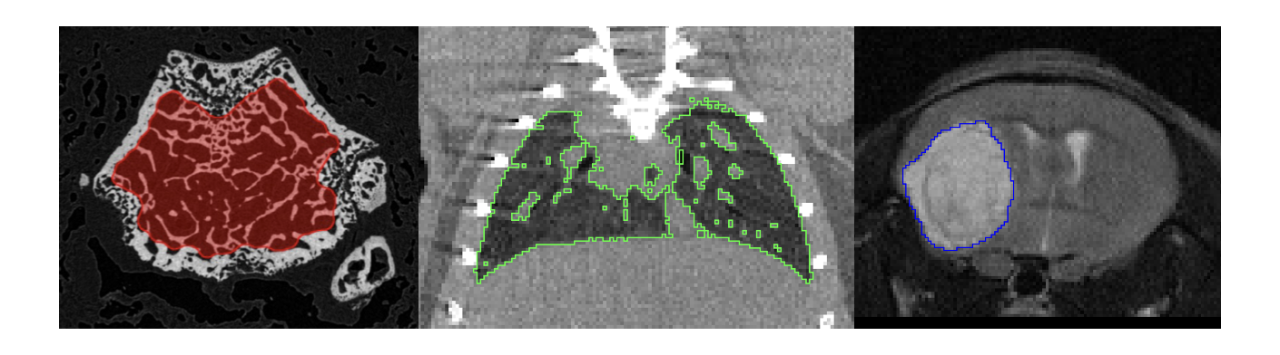

pmod’s tools provide comprehensive workflows for post-processing and quantification of imaging data for fundamental oncology research, development of radiotracers and theranostics, and in clinical research studies. Imaging scientists can trust pmod to reproducibly read their data, interpret the meta-data/units and help users calculate statistics such as SUV for their studies and publications.

• Multimodality segmentation tools – comprehensive semi-automated and manual tools for precision and reproducibility